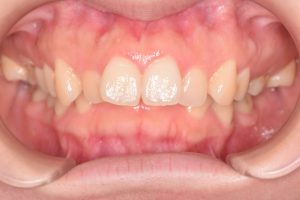

初診時(2022年9月)と装置撤去時(2025年9月)の写真です。

正面

0000000007

0000000135

・過蓋咬合

・叢生

・左右第二大臼歯シザーズバイト